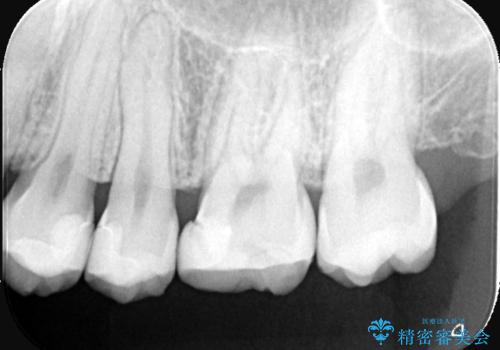

右上6番に保険適用の歯冠色材料を使ったインレーが入っていましたが、歯質とインレーとの境目に不適部位が存在しそこから二次う蝕になっていました。

おそらくCAD/CAMインレーと思われる補綴物と歯質の不適合による二次う蝕でした。また、インレーを除去したところ、側室底面の歯質の上に裏層材が一部乗っており、歯質マージンとなっていなかったこともリークの一つの原因と考えられます。